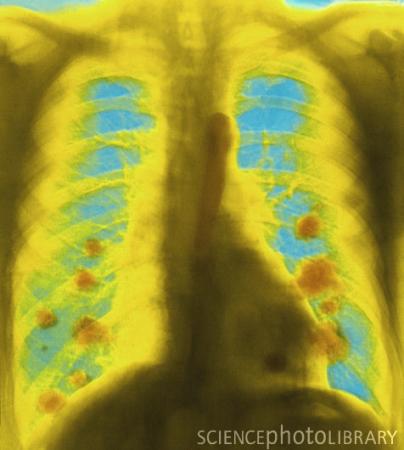

肺癌X光照相(图)